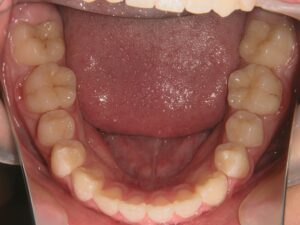

第1期治療終了時

顔貌写真

口腔内写真

治療結果

上の前歯のデコボコが改善

上の歯の狭さが改善

目標の永久歯萌出スペースを確保

第2期治療へ移行

上の前歯の裏側に保定装置(Fixリテーナー)を装着し、全ての永久歯萌出後に全顎矯正を行い、全体的な咬み合わせの調整を行います。

経過観察期間:2年7か月